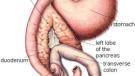

Kurkuma bojuje proti rakovině slinivky

Pravděpodobně jste již slyšeli o pozoruhodných zdravotních přínosech spojených s kulinářským kořením kurkumou a jeho antioxidační složkou kurkuminem. Nyní, nejnovější zprávy naznačují, že může mít i potenciál jako lék na rakovinu slinivky.

Rakovina slinivky břišní je 4. nejčastější příčinou úmrtí na rakovinu ve Spojených státech.

Karcinom pankreatu ničí 38.000 amerických životů každý rok a nereaguje na konvenční způsoby léčby rakoviny.